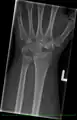

X-ray showing stage IIIB on right wrist, with ulnar impingement.